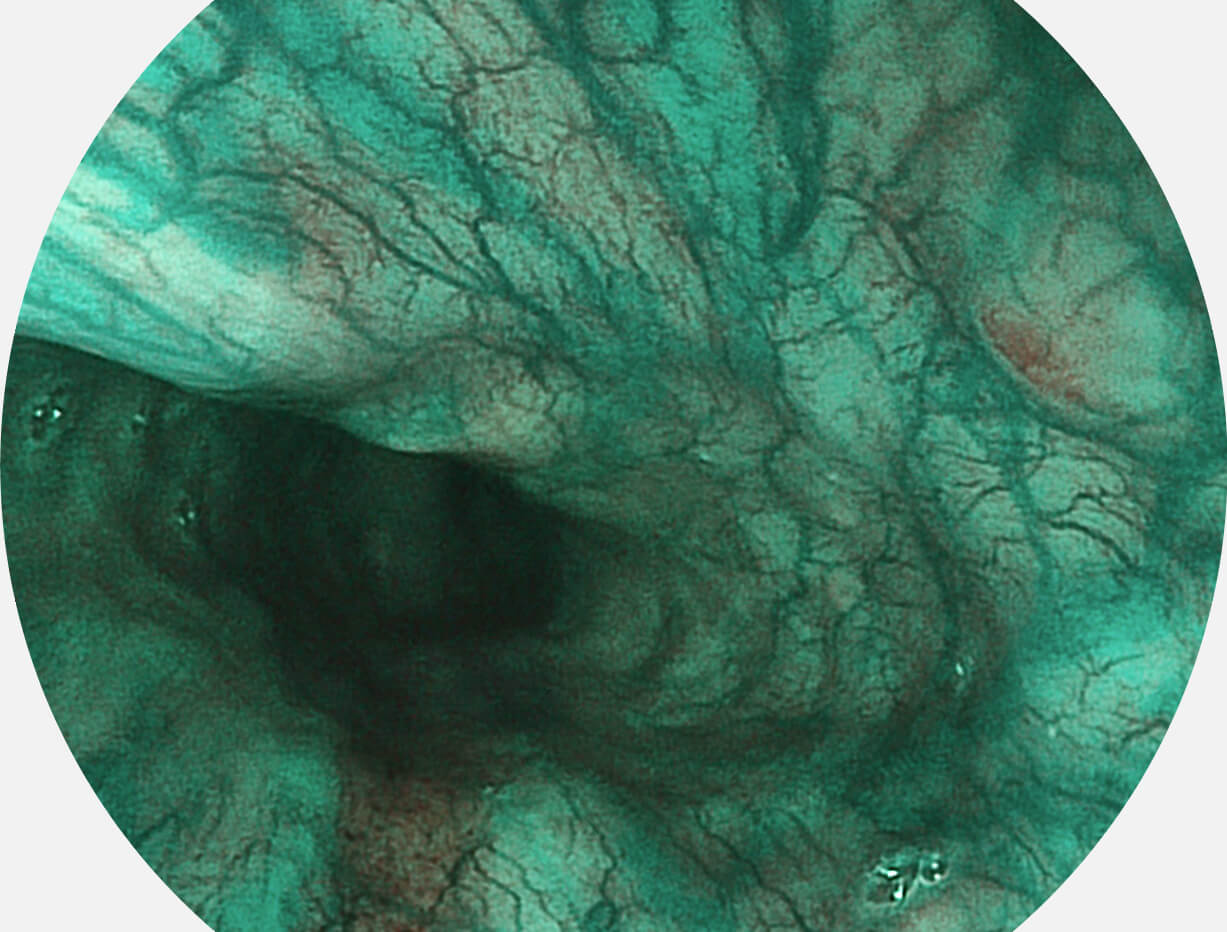

强调浅层黏膜结构的同时,保证照明亮度和提升浅层微血管与中层血管颜色对比度,病变边界更清晰。

• 白光图像 VIST图像